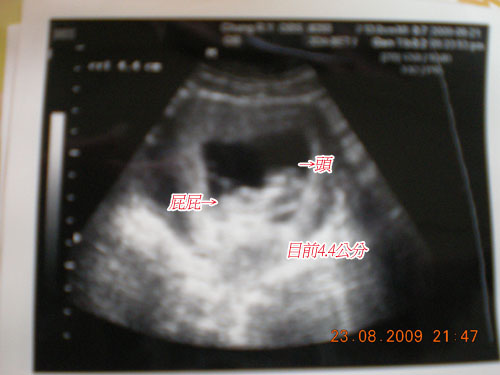

且他有4.4公分了耶~~~好好玩~還有小手小腳!!!

以下是側面照片~~~~4.4公分~~本來七八週都一樣1.4公分沒有長大~

但這次突然兩週內變大3公分= = 厲害